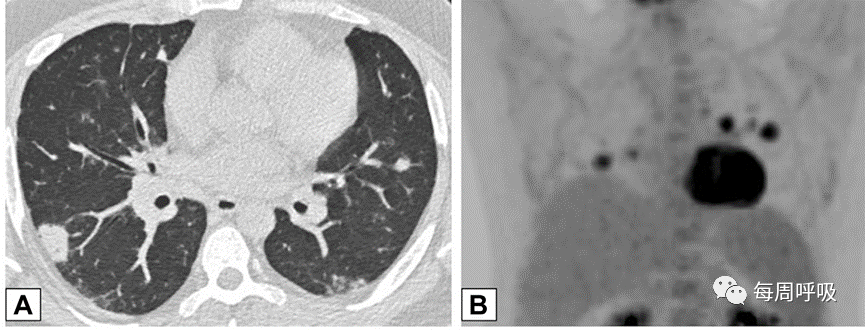

这种类型包括表现为线状不透明的实质条带,通常延伸到胸膜表面,通常先于磨玻璃样或实变(图15)。其他表现包括小叶周围增厚和具有反晕外观特征的病变(图16)。这个标志,也被称为“环礁征”,其特征是中央磨玻璃不透明(GGO)和外围实变。这些成像模式有着惊人相似的特征,通常可以在相同的情况下识别,甚至在同一张图像上。OP和慢性嗜酸性粒细胞性肺炎之间有相当多的共通之处,特别是当病变主要分布在上叶时。

图15条带活检证实为机化性肺炎的同一患者,间隔1年进行的轴位CT平扫(A)和增强(B)扫描显示,双肺下叶条带部分消退(A和B的箭头)。

图16 环礁征或反晕征。一名慢性持续性咳嗽和劳力性呼吸困难1年、体重减轻的32岁男性的CT扫描图像轴位(A)和冠状位(B)图像显示双侧中心磨玻璃样病灶完全被周围致密实变所包围,即反晕征或环礁征(A和B中红色箭头)。也存在不完全晕征(A和B中白色箭头)和小叶周围增厚(B中黄色箭头)。肺活检结果证实为机化性肺炎。

当以线性或网状为主的OP进一步发展,在周围实变或GGO后,基底和胸膜下网状形成,提示间质纤维化的发展(图17)。尽管蜂窝状和结构扭曲的发展可能表明纤维化的进展,OP也可在UIP或IPF中看到,使最终诊断复杂化。此外,OP可导致广泛的双基底牵引性支气管扩张,与背侧胸膜下肺区相对保留相关,其结果与非特异性间质性肺炎(NSIP)相似,并经常重叠(图18,图19)。

图18非特异性间质性肺炎(NSIP)。51岁女性皮肌炎患者行CT平扫。通过下肺基底的轴位(A)和矢状位(B)图像显示双肺下叶实变,双侧胸膜下和磨玻璃。矢状位图像上支气管明显扩张(B)。这些表现与机化性肺炎和NSIP重叠一致。

图19非特异性间质性肺炎(NSIP)。我们对一名病态肥胖且进行性呼吸困难的67岁男性进行了轴位CT扫描。肺基底部CT显示周围支气管壁增厚,伴有边界不清的磨玻璃密度和小叶周围增厚,特别是在左基底部(箭头),这些表现提示NSIP。外科肺活检结果与机化性肺炎相符。